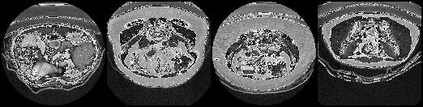

Segmentation is considered to be a very crucial task in medical image analysis. This task has been easier since deep learning models have taken over with its high performing behavior. However, deep learning models dependency on large data proves it to be an obstacle in medical image analysis because of insufficient data samples. Several data augmentation techniques have been used to mitigate this problem. We propose a new augmentation method by introducing adversarial learning attack techniques, specifically Fast Gradient Sign Method (FGSM). Furthermore, We have also introduced the concept of Inverse FGSM (InvFGSM), which works in the opposite manner of FGSM for the data augmentation. This two approaches worked together to improve the segmentation accuracy, as well as helped the model to gain robustness against adversarial attacks. The overall analysis of experiments indicates a novel use of adversarial machine learning along with robustness enhancement.